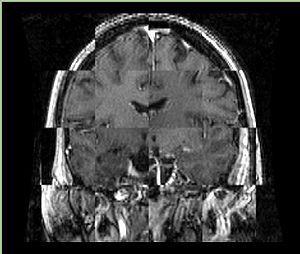

• Checkerboard appearance of unregistered images for the representative data of interest

• Case04